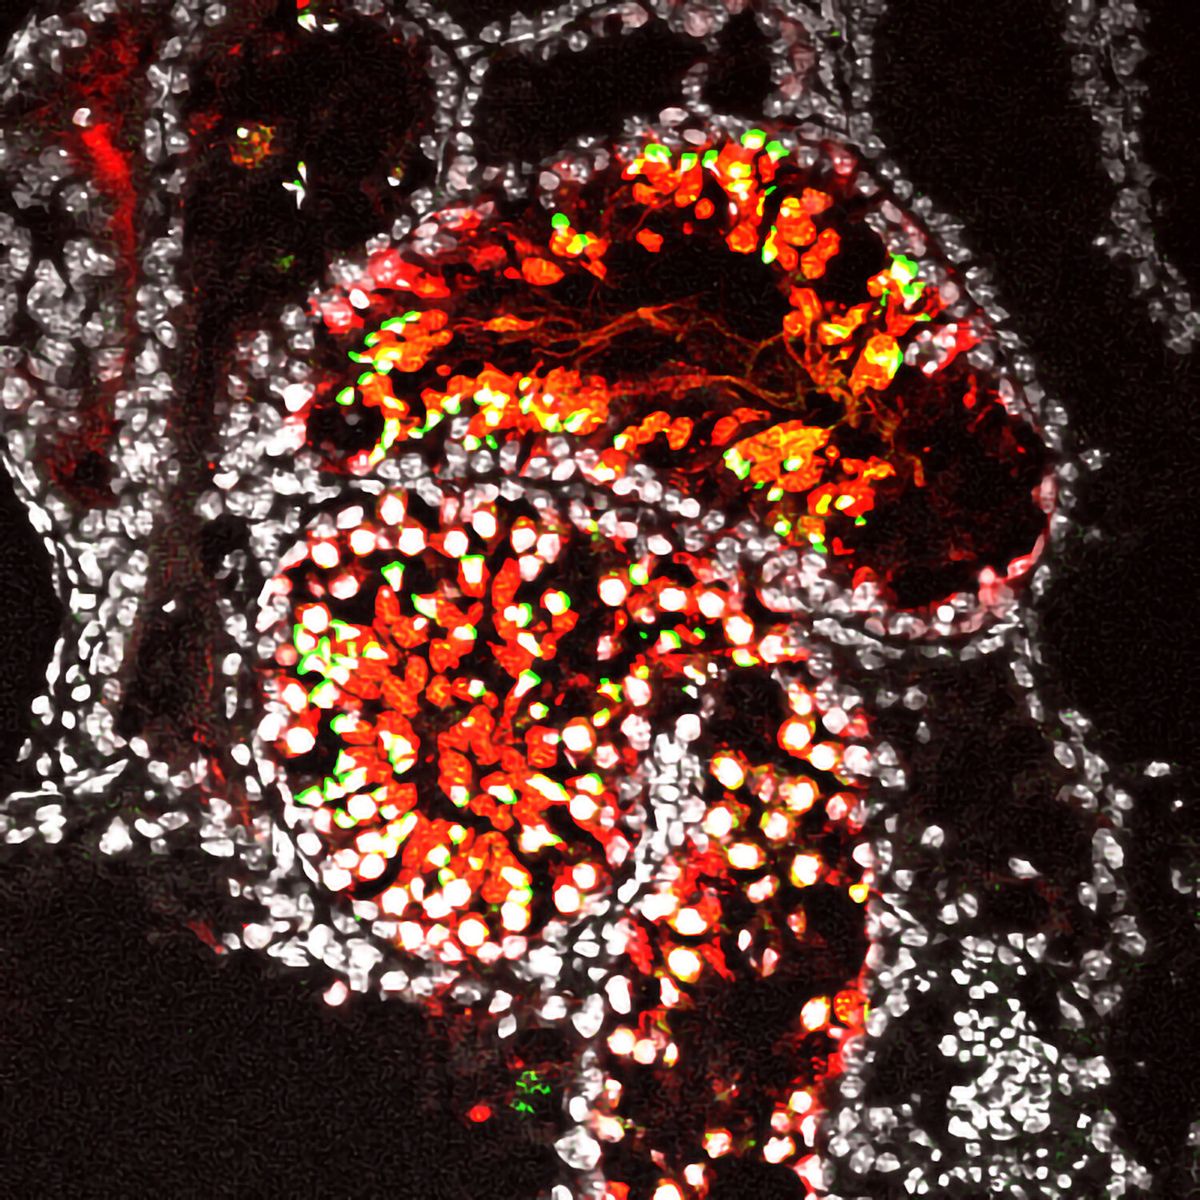

体外诱导培养52天的精子的免疫荧光染*图色**。红色表示GSCLC蛋白,绿色表示精子,白色表示细胞核。